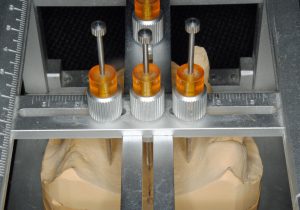

阿部晴彦先生が開発された器具で上顎模型を分析し、患者さんの顔の中の歯並びの位置関係を咬合器の中の歯並びのそれとが一致するように模型をとりつけます。

上顎の歯並びを人工歯で蝋にくっつけていきます。かみ合わせの高さも設定します。

下顎の歯並びは特殊な器具を使うと自ずと歯の位置がわかります。蝋で作っていき、プラスチックの仮歯に置き換えます。これらの一連の作業は私が行っています。